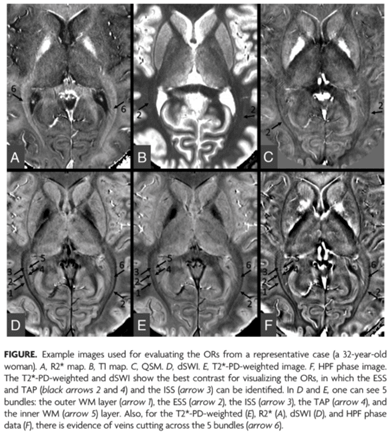

Visualization of the optic radiations is of clinical importance for diagnosing many diseases and depicting their anatomic structures for neurosurgical interventions. In this study, we quantify proton density, T1, T2*, and susceptibility of the optic radiation fiber bundles in a series of 10 healthy control participants using strategically acquired gradient echo imaging.

Furthermore, we introduce a novel means to enhance the contrast of the optic radiations using diamagnetic susceptibility weighted imaging.